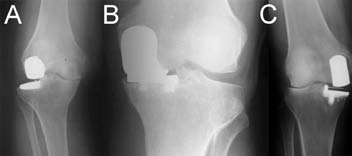

Fig. 2 Wrong component sizing or positioning may lead to edge loading (A) resulting in increased wear and implant failure (B). |

While UKA may have advantages as a surgical option for selected patients who meet the operative criteria detailed previously, TKA remains a popular operation for unicompartmental pathology. The widespread performance of UKA has been limited by the technical difficulty of performing the procedure. In particular, UKA has less tolerance for acceptable component positioning when compared to TKA, as improper component positioning, by as little as 2°, can result in UKA failure (Figure 2).[5,37,46,62-68] Failures of UKA occur when there is medial-lateral mismatch, inadequate stability of the components, heterogeneous polyethylene wear, improper patient selection (such as performing UKA for bilateral osteoarthritis), aseptic loosening, and tibial subsidence (Figure 3A and 3B).[4,27]

| Fig. 3 Disease progression of the other compartment from overstuffing, over-correction or misbalance (A), early loosening (B) and wrong component positioning may lead UKA failure. |

Improper alignment is considered to be the leading cause of UKA failure (Figure 3C).[28,61]

Maligned components often lead to impaired joint biomechanics, and eventual knee pain.[5,69,70] Reports in the literature have associated a technically poor UKA operation with accelerated polyethylene wear, an accelerated progression of the pathology to the contralateral compartment, and, in some rare instances, femoral fracture.[5,28,63,71,72,73] Strict adherence to operative technique and acceptable tolerances are required to maximize the benefits of UKA. Preservation of adequate bone stock is crucial to surgical success, leading to a shorter recovery and rehabilitation time.[25,28,45] Further, excessive bone resection often results in poor tibial component stability, which has been associated with a more difficult conversion to TKA if revision arthroplasty is eventually required.[4,68] The technical demands of performing UKA, coupled with the small margin for error, have limited the widespread adoption of this surgical intervention for unicompartmental knee pathology and many surgeons and patients remain wary of the historically inconsistent post-surgical results published in the literature.